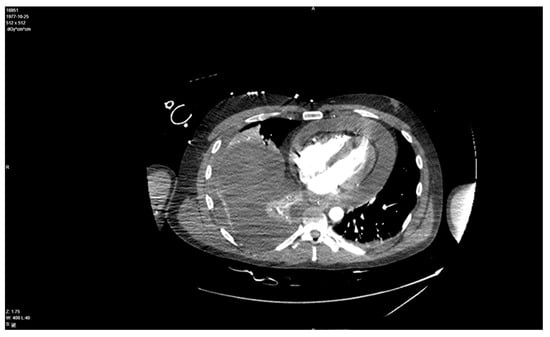

In the screening echocardiography, large pericardial effusion with signs of compression was observed, raising suspicion of cardiac tamponade (Figure 2). In addition to echocardiographic findings, the chest CT showed right-sided pleural effusion (Figure 3). A diagnosis of septic shock with multiple organ dysfunction and hypoxemic respiratory failure was made and the patient was admitted to the intensive care unit. Empiric antibiotic treatment with meropenem and vancomycin was initiated. Abdominal and pelvic CT did not show any abnormalities. Alongside the treatment for septic shock and respiratory failure, pericardiocentesis was performed and a pericardial drainage catheter was placed. About 700 mL of thick purulent fluid was drained over two days (Figure 4).

Figure 3. Chest CT demonstrates right-side effusion and a 26 mm thickness buildup of fluid in the pericardial space.